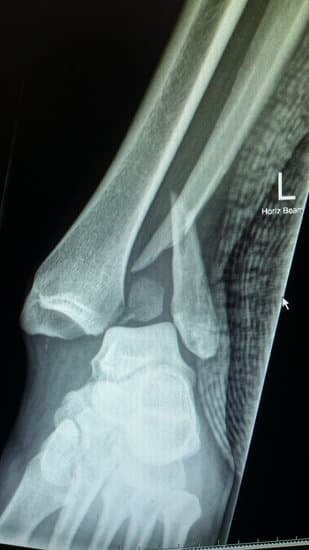

발목 골절: 원인, 증상, 치료 및 회복 과정

발목 골절은 발목을 구성하는 뼈인 경골(정강이뼈), 비골(종아리뼈), 거골 중 하나 이상이 부러지는 상태를 의미합니다.

발목 골절의 증상

기형: 심한 골절의 경우, 발목이 비정상적인 각도로 구부러지거나 변형된 상태로 보일 수 있습니다.